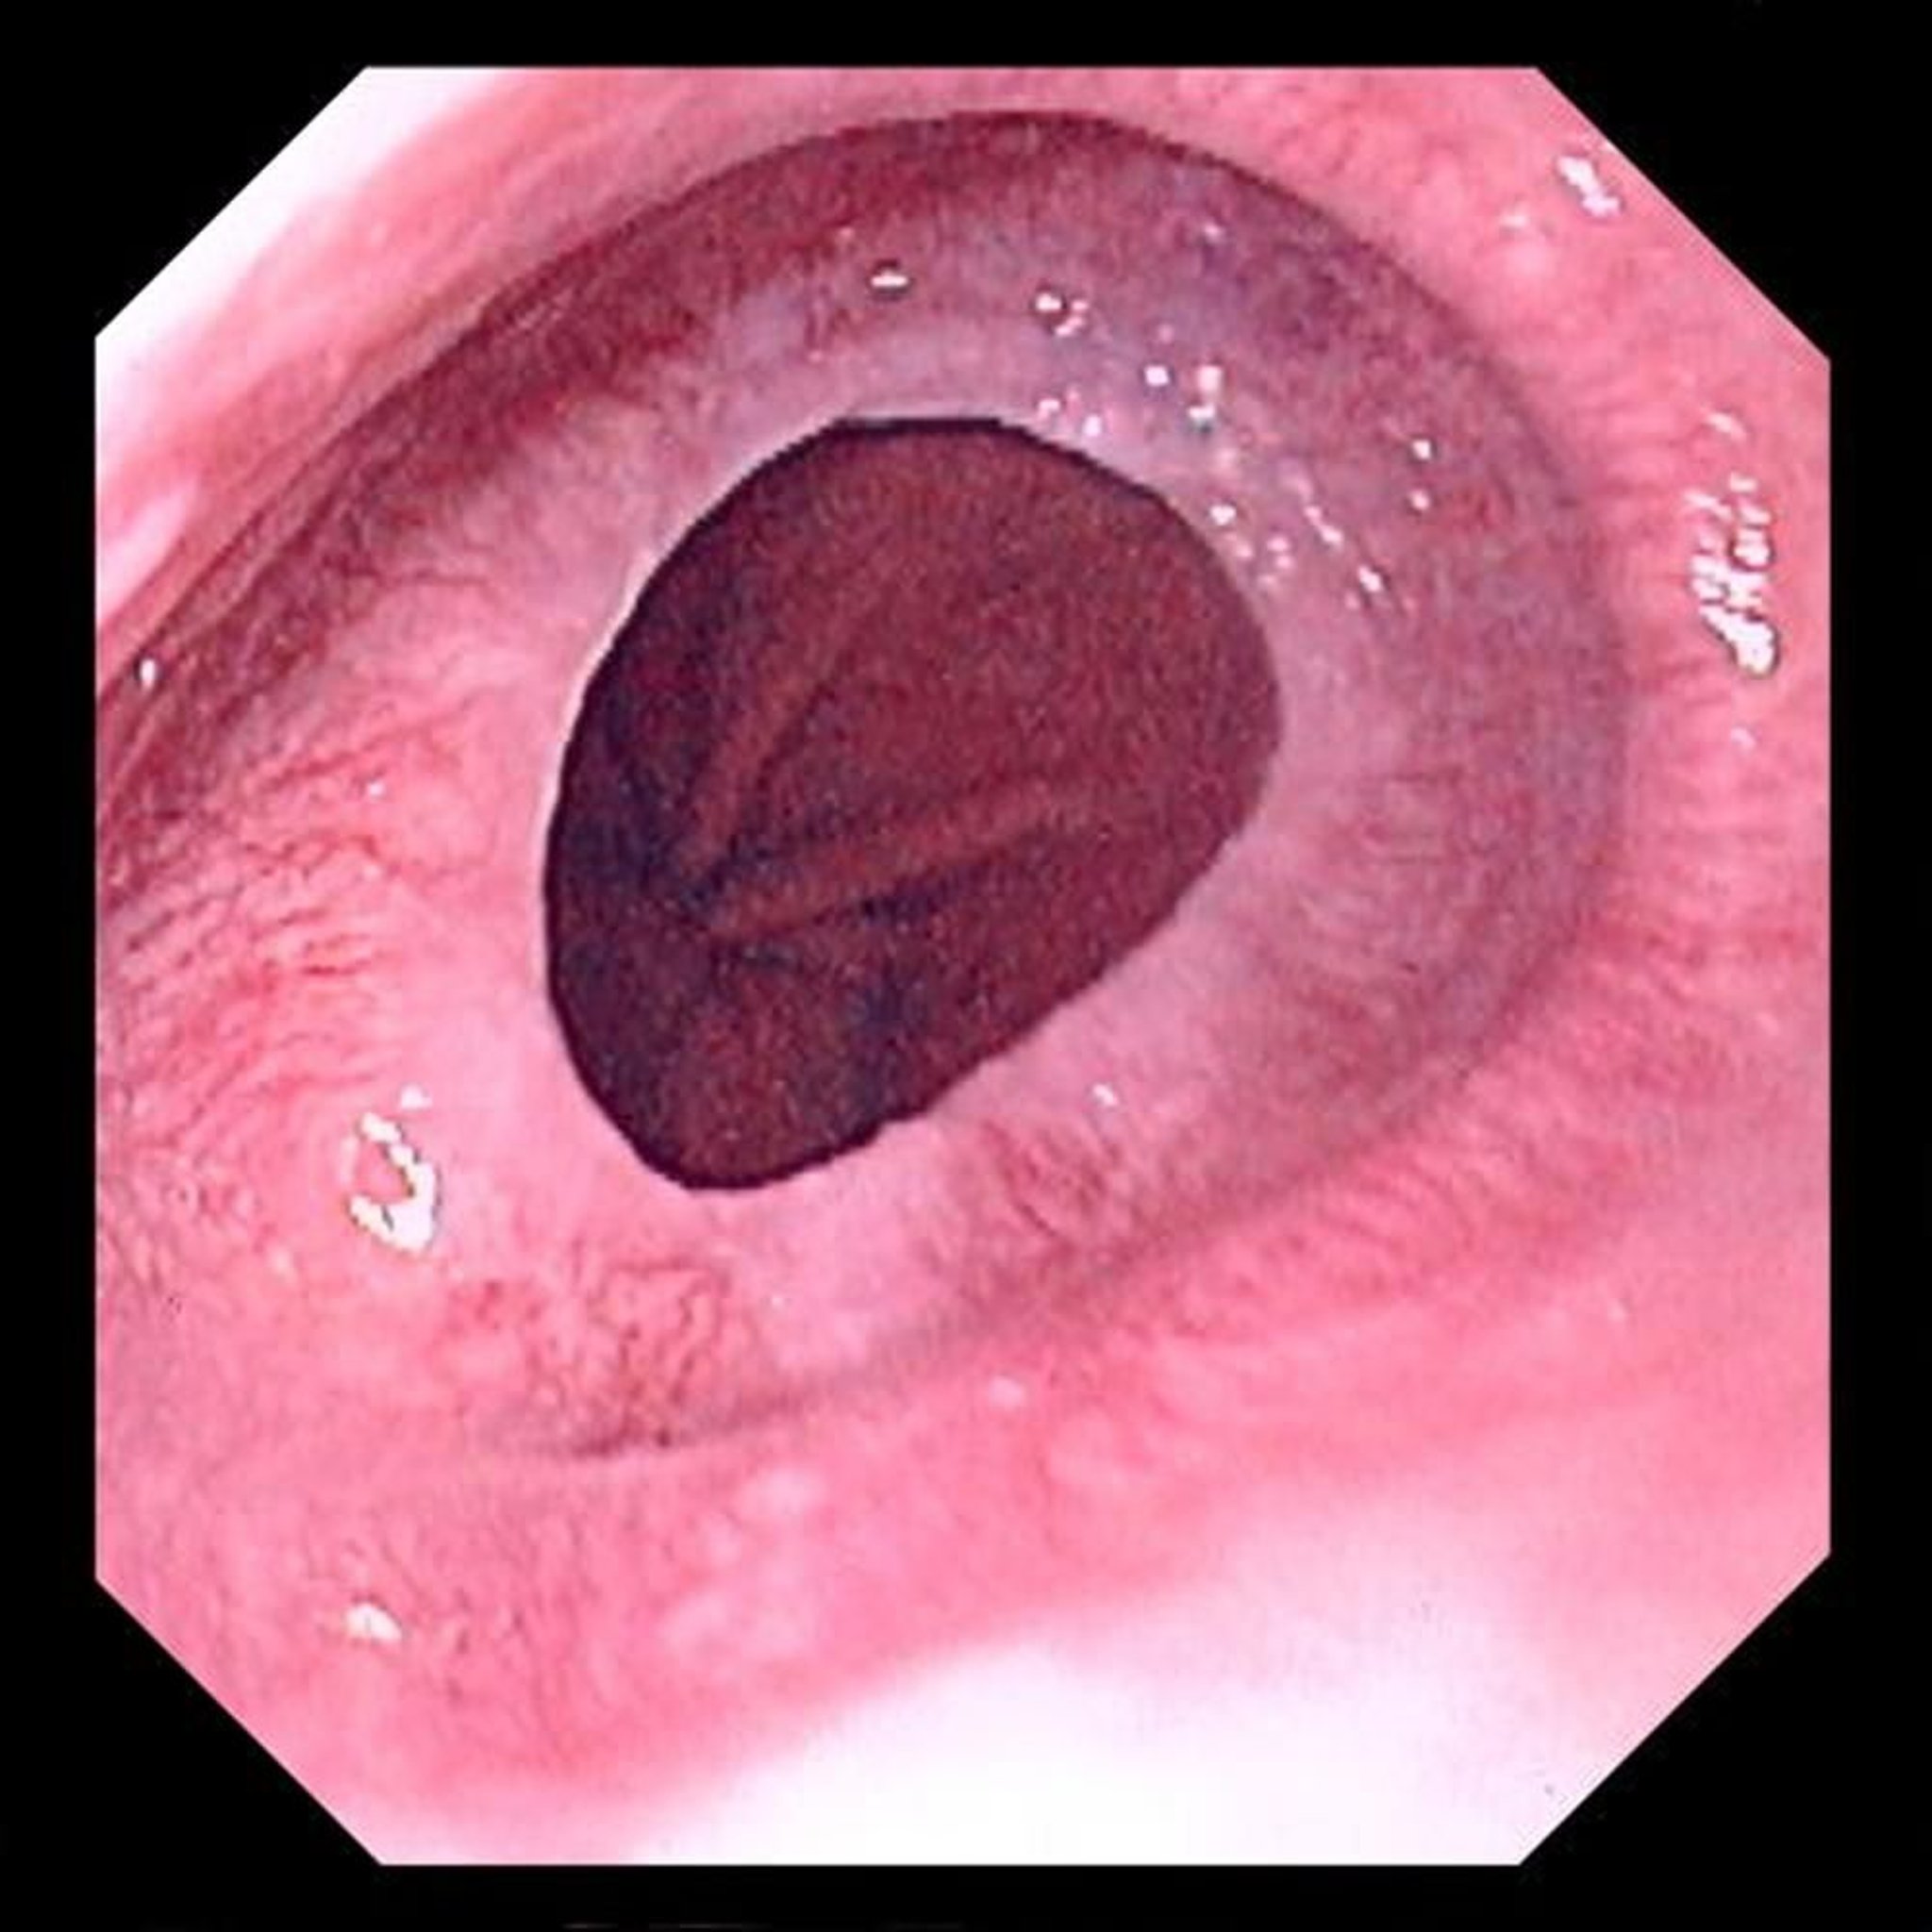

Anillo esofágico

Los anillos esofágicos (también llamados anillos de Schatzki) son pliegues lisos, concéntricos y mucosos que estrechan el esófago en la unión esofogástrica. A través de la luz de este anillo, se puede observar una hernia de hiato.

Image provided by David M. Martin, MD.